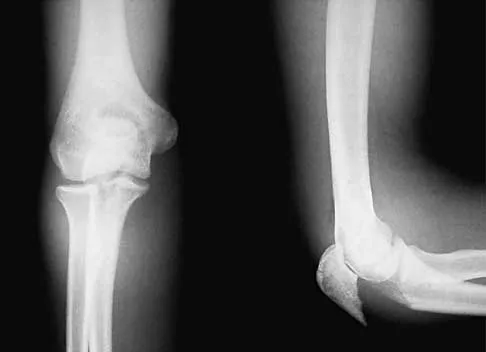

A 5-year-old boy sustained an elbow injury. Examination in the emergency department reveals that he is unable to flex the interphalangeal joint of his thumb and the distal interphalangeal joint of his index finger. The radial pulse is palpable at the wrist, and sensation is normal throughout the hand. Radiographs are shown in Figures 6a and 6b. In addition to reduction and pinning of the fracture, initial treatment should include

Explanation

The findings are consistent with a neurapraxia of the anterior interosseous branch of the median nerve. This is the most common nerve palsy seen with supracondylar humerus fractures, followed closely by radial nerve palsy. Nearly all cases of neurapraxia following supracondylar humerus fractures resolve spontaneously, and therefore, further diagnostic studies and surgery are not indicated. Cramer KE, Green NE, Devito DP: Incidence of anterior interosseous nerve palsy in supracondylar humerus fractures in children. J Pediatr Orthop 1993;13:502-505.